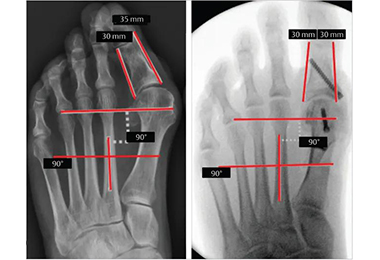

• Chirurgie mini-invasive de l'hallux valgus

2025-03-21

L'hallux valgus est une déformation osseuse à la base du gros orteil, caractérisée par une déviation latérale de l'orteil et une saillie douloureuse de l'articulation métatarsophalangienne (MTP). Bien que des traitements non chirurgicaux comme des orthèses ou des modifications de chaussures puissent atténuer les symptômes, la chirurgie est souvent recommandée pour En savoir plus